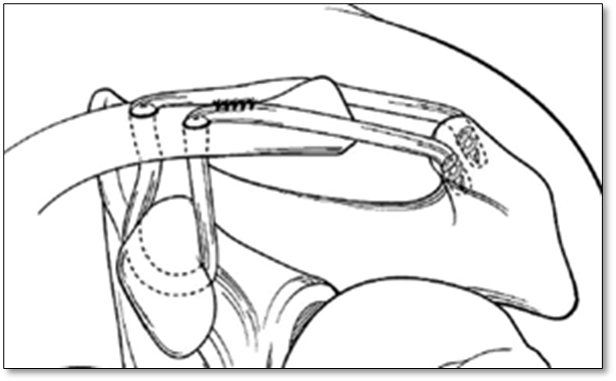

Hình ảnh tái tạo dây chằng quạ đòn bằng gân tự thân

Không theo giải phẫu: chuyển dây chằng quạ cùng.

Theo giải phẫu: Gân kheo tự thân, gân cơ chày trước đồng loại

Đây là phương pháp ưu thế hơn cả đòi hỏi kĩ thuật cao, phẫu thuật viên phải có kinh nghiệm vì phương pháp này yêu cầu:

- Cố gắng đạt được cấu trúc giải phẫu của dây chằng quạ đòn

- Cung cấp khung sườn sinh học cho tái phân bố mạch máu để tái tạo dây chằng mới